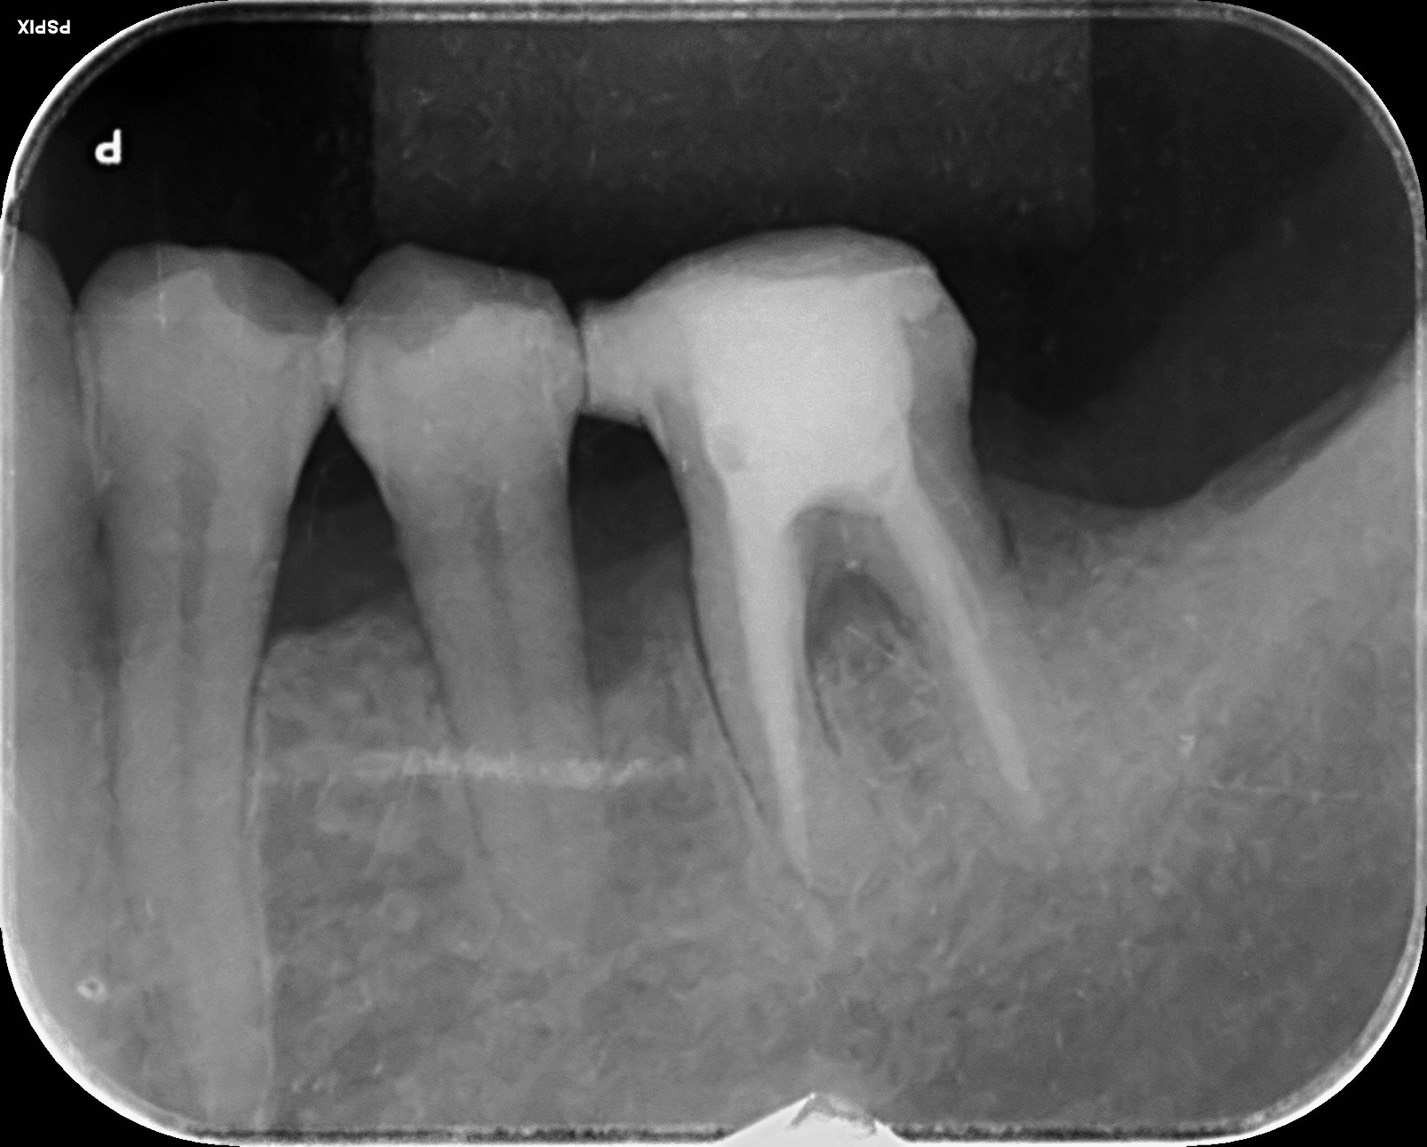

- 6.8 [20代男性]歯が折れた[歯の移植]